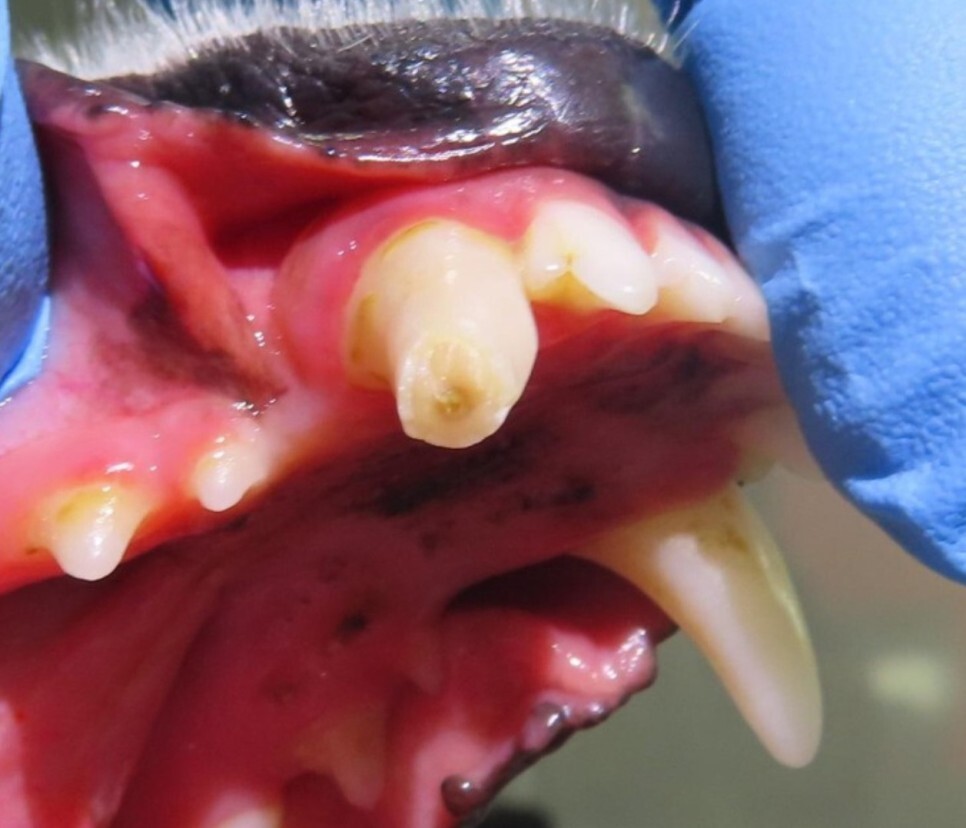

오늘은 아래턱 송곳니 골절로 인해 신경(근관)

치료를 진행한 아이 사례를 소개해 드리겠습니다.

평소 마당에서 놀면서 나무를 갉는 습관이

있는 아이라고 하셨습니다.

치아가 군데군데 깨져있는 것은 알고 계셨으나

치수가 노출된 것을 발견하고 내원을 하셨습니다.